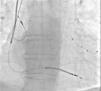

Figure 2.

Angiogram showing the successfully repositioned atrial pacing lead.